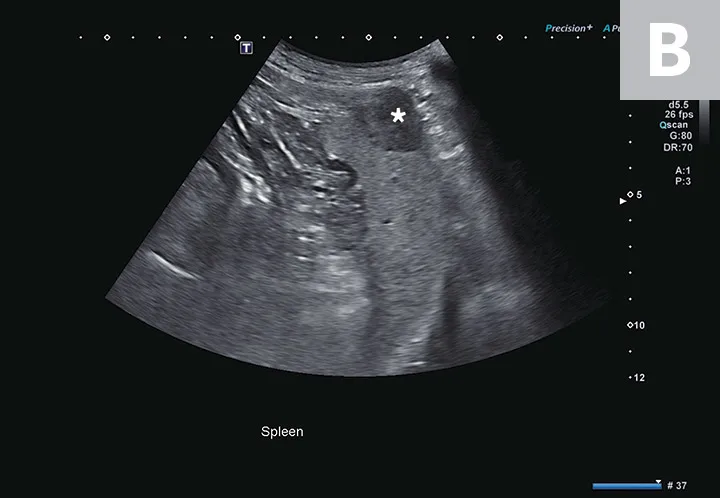

Two ultrasound images showing hypoechoic fluid adjacent to the spleen and to the heart.

FIGURE 2

Abdominal effusion (A; asterisk) adjacent to a normal spleen (arrow). Abdominal carcinomatosis with secondary neoplastic effusion was diagnosed. Left parasternal short-axis view of a heart with pericardial (B; asterisks) and pleural effusion (arrow).

The abdomen is most commonly evaluated with the patient in dorsal or lateral recumbency, but scanning the dependent portion with the patient in lateral recumbency can be helpful if only a small amount of effusion is present (see Suggested Reading).6,7 Evaluation for pleural effusion is performed with the patient standing or in ventral recumbency and should begin at the eighth to ninth intercostal space at the level of the costochondral junction. This space is also recommended when thoracocentesis is used in these patients.8 Evaluation for pericardial effusion in the right third to fifth intercostal space at the level of the costochondral junction provides the best acoustic window to the heart.5

Cavitary effusion is normally anechoic on ultrasound but can differ based on fluid type.6 Echogenicity and cytologic classification of effusion is based on cellular and protein content, increasing in echogenicity from pure transudate (anechoic) to modified transudate (variably echoic) and exudate (hyperechoic)6,9; however, the echogenicity of cavitary fluid can vary; thus, fluid analysis is required to confirm the exact nature of the fluid.